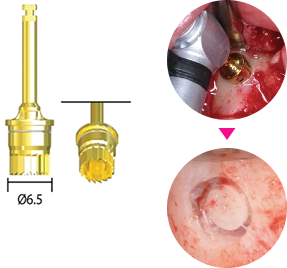

Стоппер-ограничитель

Артикул

Длина (мм)

Длина (мм)

CDS010

1

1

CDS020

2

2

CDS030

3

3

CDS040

4

4

CDS050

5

5

CDS060

6

6

Артикул

Длина (мм)

Длина (мм)

CDS070

7

7

CDS080

8

8

CDS090

9

9

CDS100

10

10

CDS110

11

11

CDS120

12

12